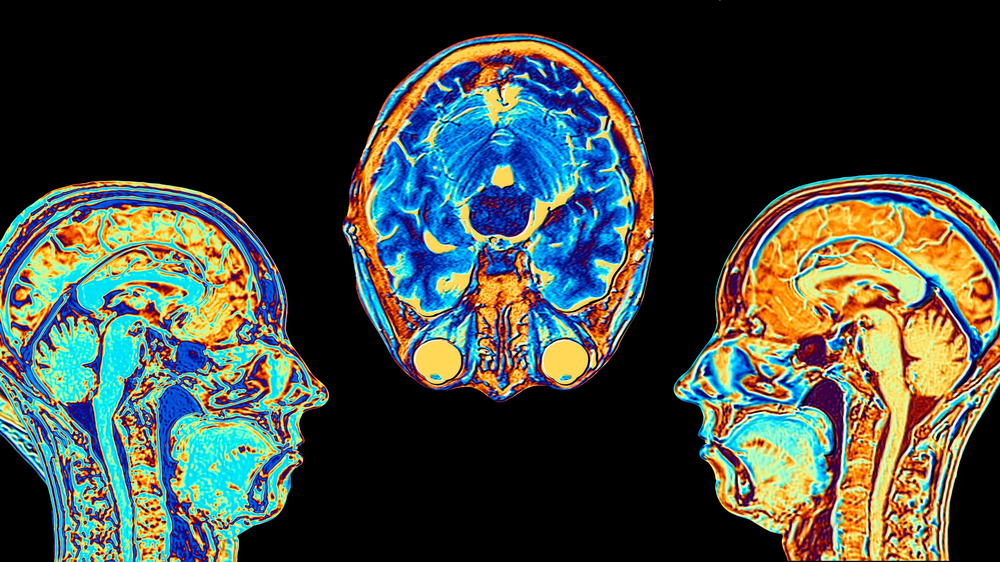

El doctor Estol comenzó su exposición aclarando que "el optimista es un pesimista mal informado", pero luego detalló los descubrimientos científicos que muestran claras diferencias en el funcionamiento cerebral. El especialista explicó que la resonancia magnética funcional permite observar no solo la estructura del cerebro, sino también su funcionamiento y activación en tiempo real.

Según detalló, los optimistas tienen mayor actividad en la corteza frontal, área responsable de la función ejecutiva, el planeamiento y la organización de acciones. "Optimista, hacés cosas", sintetizó el neurólogo de manera contundente. Además, los optimistas presentan mayores niveles de dopamina, el neurotransmisor relacionado con la motivación y la recompensa, y poseen más materia gris en núcleos cerebrales vinculados con la empatía, el manejo de conflictos y las emociones.

En contraposición, los pesimistas muestran mayor actividad en la amígdala cerebral, núcleo que gestiona el miedo y las emociones negativas. También presentan niveles más elevados de cortisol, la hormona del estrés, y menor cantidad de materia gris en la corteza frontal encargada de la planificación.

"Los pesimistas tienen la amígdala activada, más cortisol y menos corteza gris en la zona que se ocupa de llevarte a hacer cosas", explicó Estol, describiendo así el patrón neurológico que caracteriza a estas personalidades.